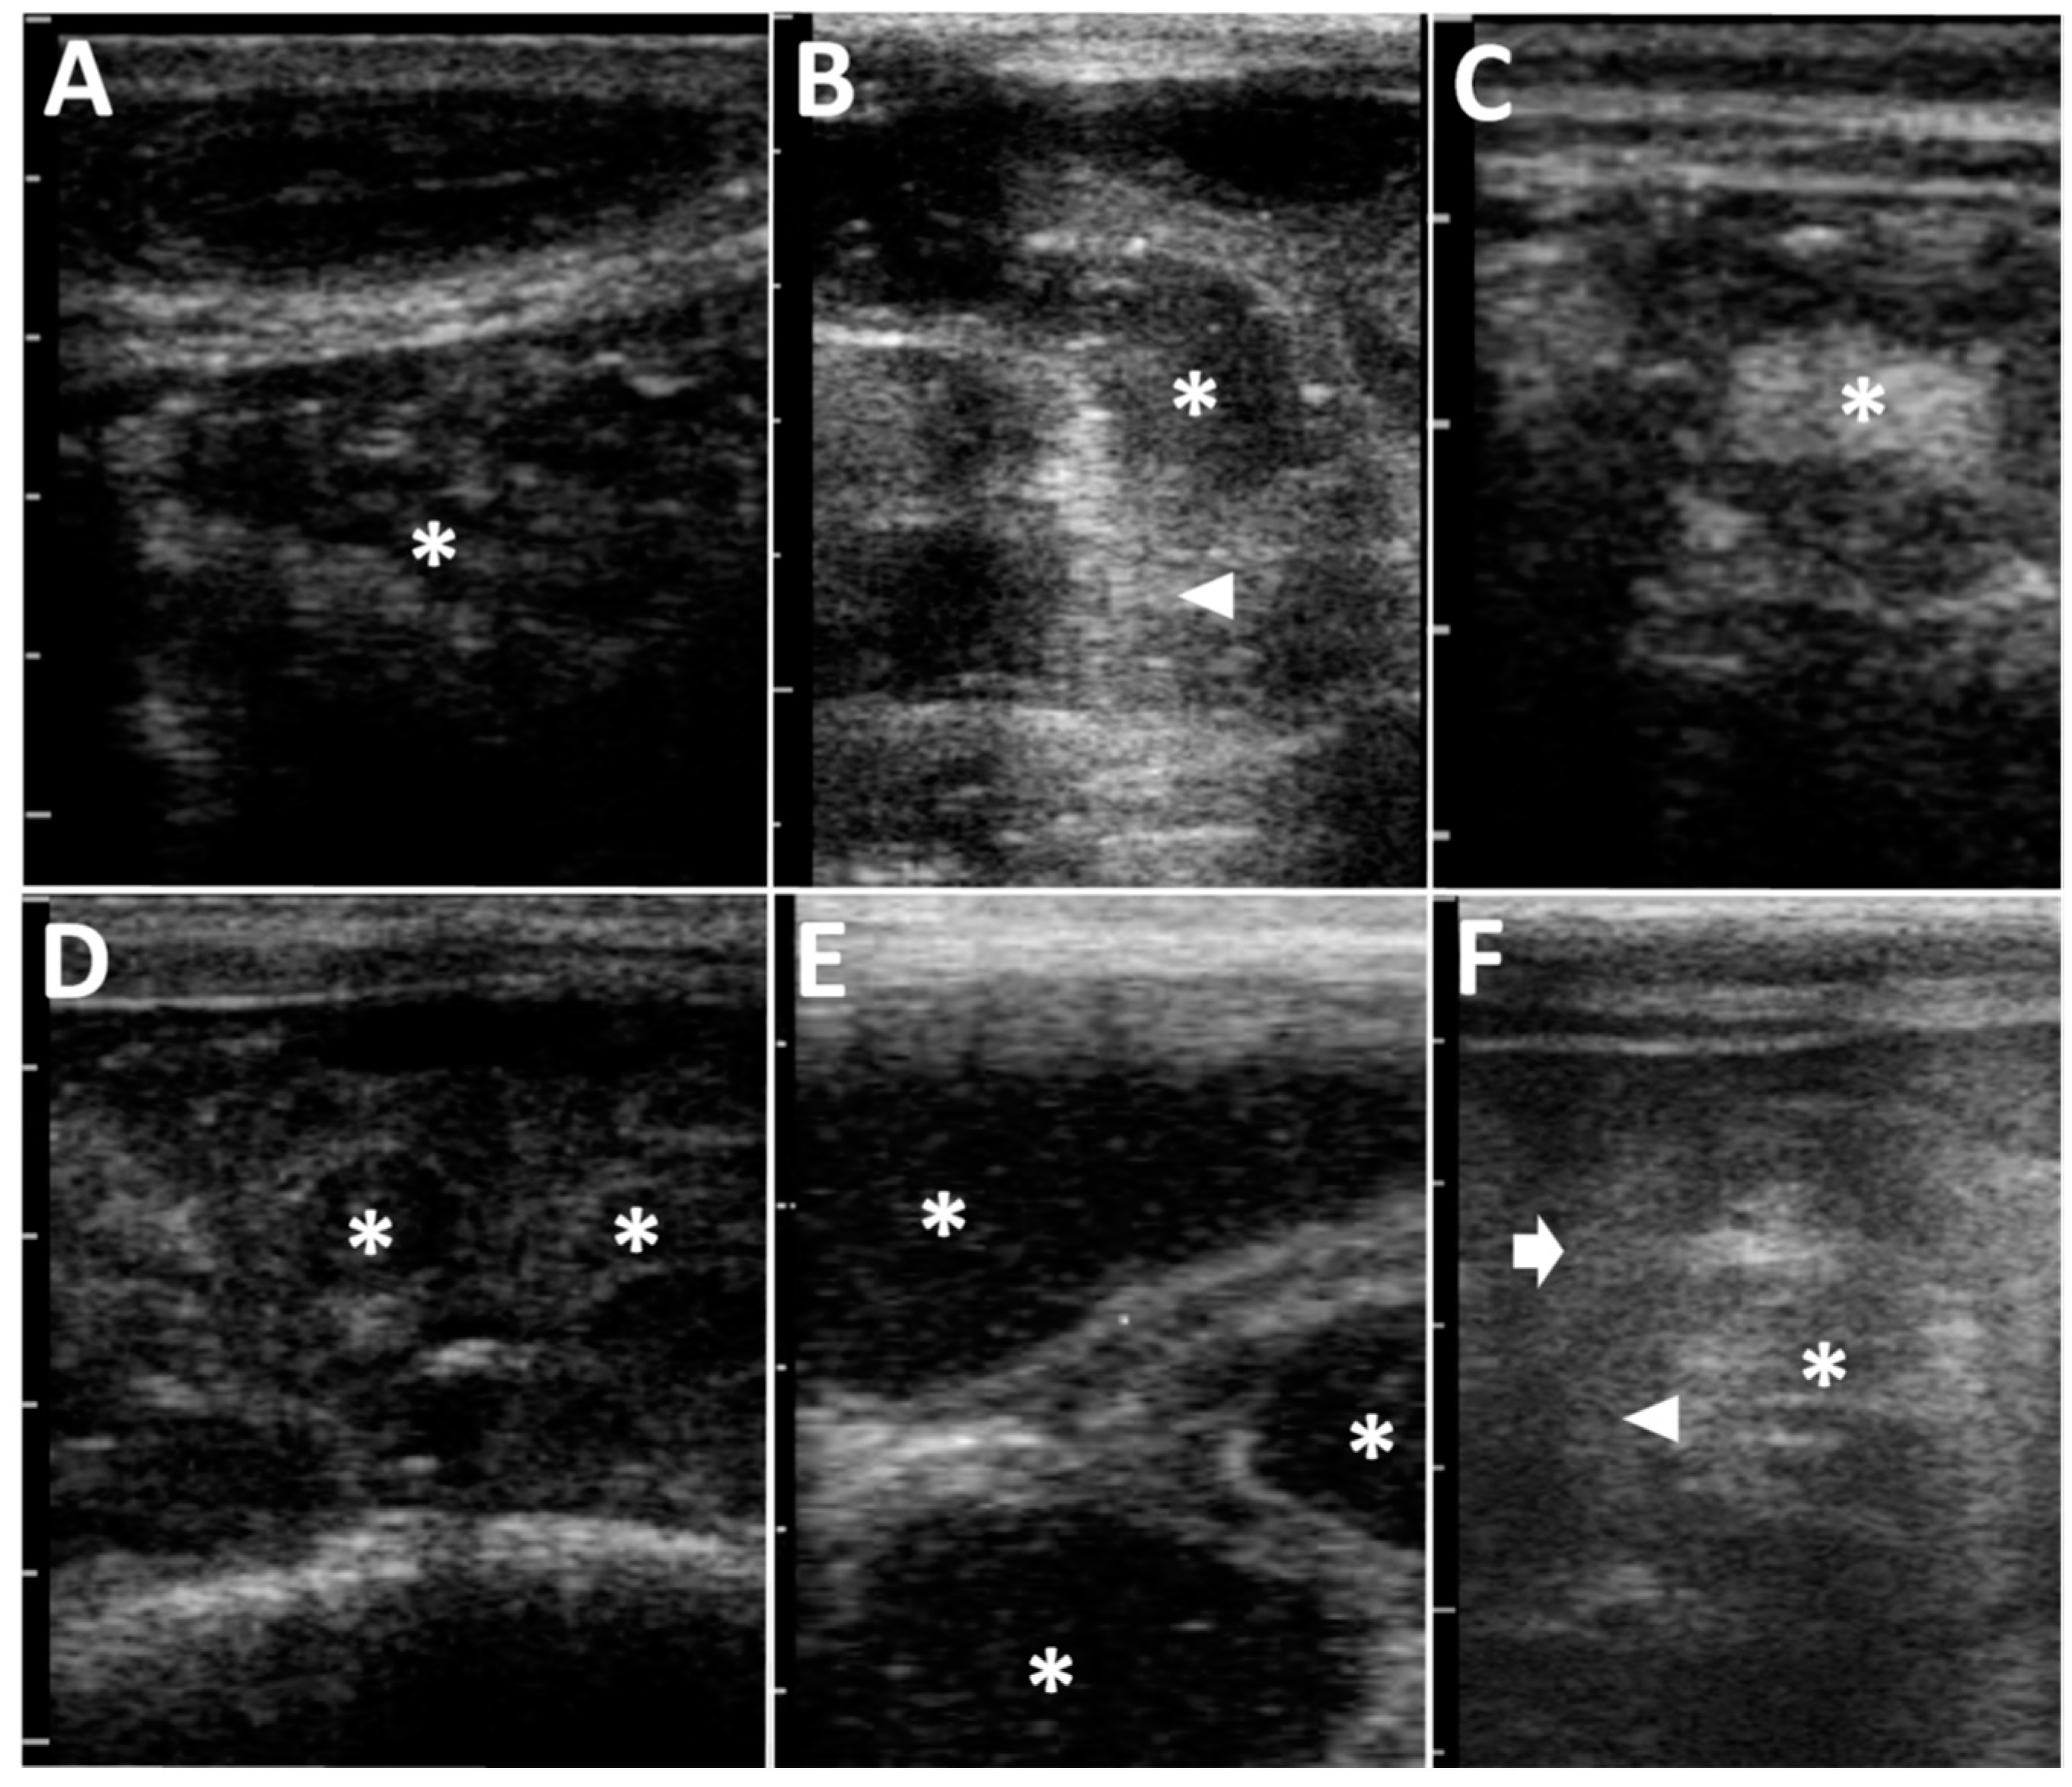

Figure 2. Abdominal ultrasonograms of Case 2 (A), Case 4 (B), Case 5 (C), Case 6 (D), Case 8 (E), and Case 9 (F). (A) The heterogeneously hypo- and hyper-echoic ingesta, including hyperechoic deposits, are seen to fully fill within the severely dilated lumen of the abomasum (asterisk). (B) In a longitudinal section, the dilated intestine includes the hypoechoic fluid contents with multiple hyperechoic deposits (asterisk). An acutely angled narrowing (arrowhead) is evident in the dilated, acutely curved intestinal loop. (C) In a cross section of the round, dilated intestinal loop, the hyperechoic contents (asterisk) are included in the thickened, hypoechoic wall. (D) The intraluminal contents are hypoechoic (asterisks) in multiple cross-sections of the dilated intestinal loops. (E) The hypoechoic contents with hyperechoic spots are included in the 1.5- to 3.0-cm-thick lumens of multiple, dilated intestinal loops (asterisk) seen on the same screen. (F) In the cross-section of the affected loop, the heterogenous hypo- and hyper-echoic contents (asterisk) are seen within the lumen surrounded by the thickened, hypoechoic, double, intestinal walls comprising of intussusceptum (arrowhead) and intussuscipiens (arrow). Scale bar = 10 mm.

In terms of the clinical signs in Cases 1–3, two animals (Case 2 and Case 3) had abdominal distention in the ventral levels of their right flanks, although there was no evidence in their left flank (Table 1 and Figure 1A). Cases 1–3 had the normal defecation and no signs of dehydration. Auscultation identified splashing sounds at regular intervals within the ventral levels of their right abdomens, despite no ping sound being induced by percussion in Cases 1–3 (Table 2). In all three cases, ultrasonography of the ventral areas of their right abdomens revealed that the ingesta were fully contained within the severely dilated abomasal lumens (Figure 2A). The abomasal ingesta were ultrasonographically characterized by a heterogeneous mixture of hypoechoic and hyperechoic contents. No intraluminal accumulations of gas were evident, as there were no ultrasonographic appearances of posterior acoustic shadowing. The areas of the pylorus could not have been demonstrated. No abnormal distention was evident in the small intestinal loops when scanned at the caudal and ventral areas of the right abdomen. Thus, these three cases (Cases 1–3) were suspected to have abomasal dilation. Conservation therapies for these animals enabled rapid improvements in their clinical signs, resulting in favorable outcomes.

In Cases 4–8, two cases (Case 4 and Case 5) had no evidence of abdominal distention, despite presenting with severe depression, resulting in them laying down (Figure 1B, Table 1). Abdominal distention of the right flank and both flanks were found in two cases (Case 6 and Case 7) and one case (Case 8), respectively (Figure 1C). Auscultation identified a splashing sound in all five animals with intestinal volvulus. A ping sound could be heard in one of five animals (Case 8) when examined by auscultation. Abdominal ultrasonography for Cases 4–8 showed for all animals findings of severe dilation of the small intestinal loops in the ventral area of their right abdomen. On the ultrasonograms showing cross-sections of the dilated loops, >2 loops could be imaged on the same screens (Figure 2B). In Case 4, on the longitudinal ultrasonogram showing the acutely curved dilated intestinal loop, the lumen was narrowed with an acute angle from the dilated, orad parts, due to gentle manual rotation of the transducer (Figure 2B and Table 2). In the four of five animals with intestinal volvulus (Cases 5–8), this finding was not observed in the ultrasonograms showing the longitudinal sections of the dilated intestinal loops. In Case 5, on a cross section of the round, dilated intestinal loop, the intestinal wall was severely thickened to approximately 5 mm throughout its whole circumference (Figure 2C). The hyperechoic contents were included within a 5-to-10-mm dilated lumen, surrounded by the thickened, hypoechoic wall. At the cross section of the maximum dilated part, the diameter was 3.5 cm (Table 2). In common with the ultrasonographic findings in Cases 6–8, multiple cross sections of the dilated intestinal loops could be observed on one screen of the ultrasonogram (Figure 2D,E). The intraluminal contents were demonstrated as hypoechoic with or without hyperechoic spots. On the ultrasonograms in Cases 6–8, no peritoneal effusion could be identified between the intestinal loops’ spaces. A to-and-fro flow was commonly demonstrated in the dilated lumens of the longitudinal sections of the intestinal loops of all five animals (Cases 4–8) (Video S1). Additionally, ultrasonography revealed no evidence of propulsive contraction in all five animals (Cases 4–8). Based on their clinical data, for Cases 4–7, laparotomy was the chosen therapeutic option.

In Case 9, abdominal distention was not evident in either flank (Figure 1D), when abdominal pain initially presented (Table 1). The farmer noted that the animal had completely ceased to pass feces. Auscultation identified splashing sounds but no ping sounds (Table 2). Abdominal ultrasonography identified a to-and-fro flow of ingesta into the dilated lumen of the longitudinal-sectional loops. The gentle rotation of a transducer from the scanning position to the longitudinal view allowed observation of the cross-section of a 4-cm-thick, circular loop of the affected part, including 1.5-cm-thick lumen, in which the intraluminal contents could be observed as a heterogenous mixture of hyper- and hypo-echoic. The hypoechoic wall of the affected part was a double-layered structure, 5–7-mm-thick (Figure 2F). This finding was recognized as a target sign, despite the intestinal walls of the invaginated loop being slightly unclear. When performing laparotomy based on the ultrasonographic suggestion of intussusception, the affected intestinal loop can be detected between the spaces of the dilated intestinal loops via the surgical opening. Within the affected part, the engulfed, orad portion exhibited normal elasticity and hardness, despite its dark red discoloration (Figure 3E). The distal portion had no discoloration, and normal elasticity in the intestinal loop located in the orad region. Manual reduction allowed the engulfed portion to be smoothly pulled out from the invaginated portion. The animal had a favorable outcome following surgery.

In Case 10, the abdominal distention was very severe in both its flanks. The animal exhibited severe pain and no defecation. Auscultation identified ping sounds over the entire area of both sides of its swollen flanks, although no splashing sounds were heard (Table 2). Ultrasonograms of its right abdomen showed intraluminal gas within the dilated intestinal loops, measured to have a maximum diameter of 3.7 cm. Being located proximally to the skin’s surface, this generated reverberation artifacts, resulting in unclear images of the intestinal loops located more distally. Gently moving the transducer allowed observation of the dilated loops, including swirling flows of intraluminal ingesta in the spaces between the dilated, gas-filled loops. A to-and-fro flow motion was not ultrasonographically evident. Exploratory laparotomy was carried out on the day of examination. The affected intestinal loop was observed as a ball-like mass, located deeper than the multiple gas-filled dilated loops seen via the surgical opening. In the macroscopic view of the mass, the dilated loop curved acutely, making a 180° turn, followed by incarceration of the turned loop through the hole in the mesentery (Figure 3F). The reduction of the incarcerated loop was achieved following the cutting of the mesentery to make the hole wider. The incarcerated part was dark red in color. An end-to-end anastomosis was performed following resection of the discolored loop. However, the animal was dead four days after the surgery, although the reason for its death following discharge was unknown.